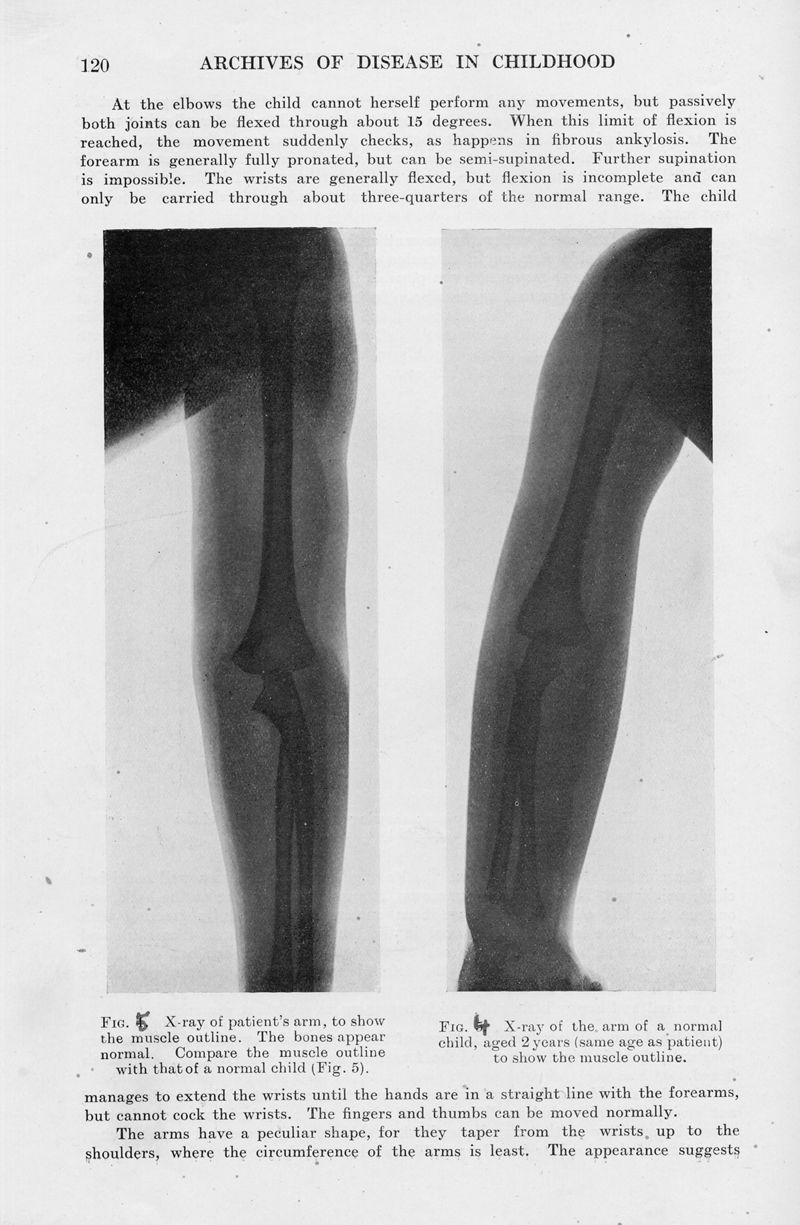

Amyoplasia congenita. (Multiple congenital articular rigidity : Arthrogryposis multiplex congenita)

In : Archives of Disease in Childhood, 1932, Vol. 7, pp. 117-36